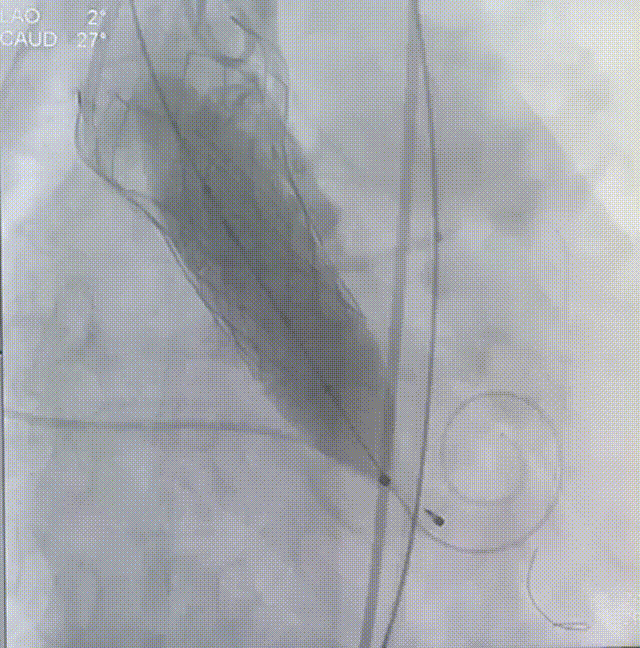

术中操作

主动脉根部造影

22mm球囊预扩

瓣膜定位

瓣膜释放

瓣膜锚定

瓣膜完全释放

24mm球囊后扩

完成植入

术后即刻超声显示:释放后瓣膜工作正常,DSA下未见瓣周漏,植入效果良好。患者的跨瓣压差由术前的89mm/Hg改善至术后的2mm/Hg,患者获益明显。